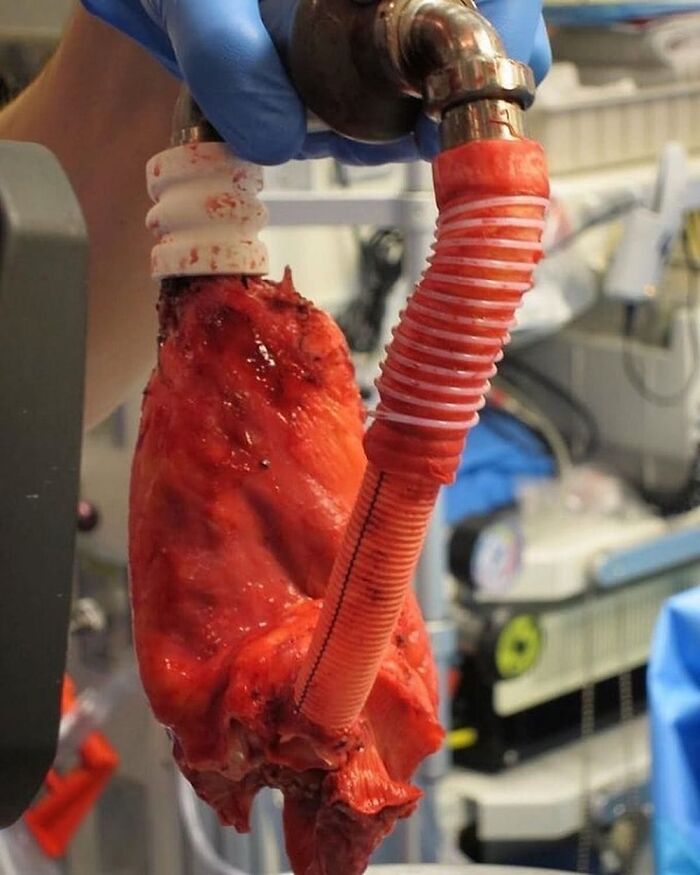

A Blood Clot Coughed Up By A Patient, That Perfectly Shaped The Lung’s Cavity It Filled

This huge blood clot took the shape of the bronchial tree. This photo shows the most visually arresting medical anomalies. The image is of a mysterious, branchlike structure that, posted elsewhere, would probably pass for a cherry-red chunk of some underground root system or a piece of bright reef coral. But this is no creature of the deep. It’s a completely intact, six-inch-wide clot of human blood in the exact shape of the right bronchial tree, one of the two key tubular networks that ferry air to and from the lungs. And it was coughed up in one piece. This cast was produced by a 36-year-old man who was admitted to the intensive care unit with an acute exacerbation of chronic heart failure. His medical history included heart failure with an ejection fraction of 20%, bioprosthetic aortic-valve replacement for bicuspid aortic stenosis, endovascular stenting of an aortic aneurysm, and placement of a permanent pacemaker for complete heart block. An Impella ventricular assist device was placed for management of acute heart failure, and a continuous heparin infusion was initiated for systemic anticoagulation. During the next week, the patient had episodes of small-volume hemoptysis and increasing respiratory distress. During an extreme bout of coughing, the patient spontaneously expectorated an intact cast of the right bronchial tree. Terrifying as it is, it's a fascinating illustration of the anatomy of the right bronchial tree, which consists of three segmental branches in the upper lobe (blue arrows), two segmental branches in the middle lobe (white arrows), and five segmental branches in the lower lobe (black arrows).